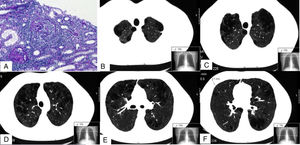

Imágenes de la biopsia renal (A) y de la TC pulmonar (B-F). En A se muestran 2 glomérulos con proliferación extracapilar o semilunas (ácido peryódico de Schiff). B, C, D, E y F son diferentes cortes de la TC pulmonar en los que se aprecia un enfisema mixto centrilobulillar bilateral, con zonas de afectación paraseptal y bullas subpleurales de predominio en lóbulos superiores. En F se puede observar uno de los nódulos de 3,1mm (línea discontinua).

Presentamos el caso de un varón de 32 años, fumador de 13 paquetes/año, sin exposición a otros tóxicos ni antecedentes familiares ni patológicos de interés, que fue diagnosticado de una vasculitis C-ANCA anti-proteinasa 3 (PR3) y un enfisema pulmonar severo. El paciente en el momento del diagnóstico presentó síntomas constitucionales, artralgias, isquemia digital en la mano y afectación renal, expresada como proteinuria no nefrótica y microhematuria con un filtrado glomerular normal. En la analítica destacó una hemoglobina de 12,2g/dl y un aumento de la VSG y proteína C reactiva. En el estudio inmunológico los C-ANCA fueron positivos, con un título de anti-PR3 de 79U/ml (valor normal <2U/ml) y anti-MPO: 0U/ml. El resto de estudios, que incluyeron los anticuerpos anti-membrana basal glomerular, ANA, complemento, inmunoglobulinas, crioglobulinas, anticuerpos antifosfolípidos, proteinograma y serologías de hepatitis B, C, VIH fueron normales o negativos. El Mantoux y quantiferón resultaron negativos. En la biopsia renal presentó una glomerulonefritis proliferativa extracapilar con formación de semilunas en un 46% de los glomérulos y pauciinmune (fig. 1A). En la TC otorrinolaringológica no se destacaron alteraciones significativas, y en la torácica 3 nódulos en el pulmón derecho inferiores a 5mm, y un severo enfisema mixto centrilobulillar bilateral difuso con áreas de afectación paraseptal y bullas subpleurales de predominio en los lóbulos superiores (figs. 1B-F). En el esputo no se encontraron hemosiderófagos. En las pruebas funcionales respiratorias destacaron DLCO: 68%, KCO: 66%, FEF 25-75%: 58%, FEV1: 80% y FEV1/FVC: 69%. Se trató con glucocorticoides a una dosis inicial de 1mg/kg/día vía oral en pauta descendente y ciclofosfamida intravenosa, según la pauta CYCLOPS3. El paciente abandonó el hábito tabáquico e inició tratamiento con broncodilatadores. Se determinaron en 2 ocasiones los niveles de alfa-1-antitripsina (AAT), que resultaron normales (140 y 145mg/dl, respectivamente) y, además, se determinaron cualitativamente mediante PCR-ARMS los alelos PI*S y PI*Z del gen de la AAT, sin detectarse ninguno en el paciente.